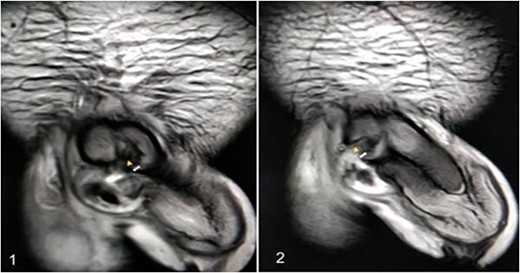

A 37-year-old male presented with a history of a ‘snap’ sound and immediate detumescence of penis during intercourse, when he fell and hit the pubic bone of his partner. There was generalized swelling and pain in the penis. There was acute retention of urine, an attempt to pass a catheter failed and the patient underwent supra-pubic catheterization. On examination, there was classical ‘eggplant deformity’ of the penis with blood at the tip of the meatus. MRI showed a tunical tear on both sides at the penoscrotal junction with indistinct urethra and extensive hematoma in the proximal penile shaft (Fig. 1). With the diagnosis of a fractured penis and possible urethral injury, after proper counselling, the patient was taken up for surgery. On the table, a retrograde urethrogram (RGU) was done showing evidence of partial urethral disruption. On exploration with penoscrotal vertical incision, there was total transection of proximal penile urethra, and a 1.5 cm tunical injury of corpus cavernosum on both sides ventrally (Fig. 2). There was extensive hematoma. Corpora sutured with 4.0 prolene after reconstructing the midline septum. Urethral ends mobilized and anastomosed with 3.0 vicryl in a single layer with minimal spatulation (Fig. 3). The patient was discharged on the 5th post-operative day; Foley catheter was removed on day 21. Follow-up RGU done after 3 months showed no evidence of stricture (Fig. 4).

(1) On table RGU showing evidence of partial urethral disruption and (2) total transection of proximal urethra on exploration with penoscrotal vertical incision.